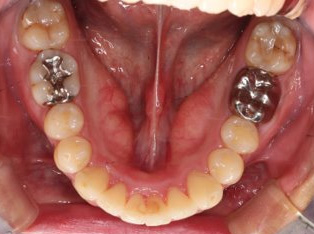

乱ぐい歯、でこぼこがとても酷い状態になります。歯が前後的に重なってしまっている、八重歯になっているなどがこのジャンルに入ります。

顎の大きさと歯の大きさのギャップが大きく、時には歯を抜かないと矯正治療ができない場合もあります。当院では治療期間が長くなるが抜かない治療方針など、一つの治療プランだけでなく、さまざまな可能性の治療方針を説明させて頂くよう心掛けております。こういった考え方はインフォームド・チョイスと言われ近年大切にされている考え方と言われております。

治療前

治療終了前